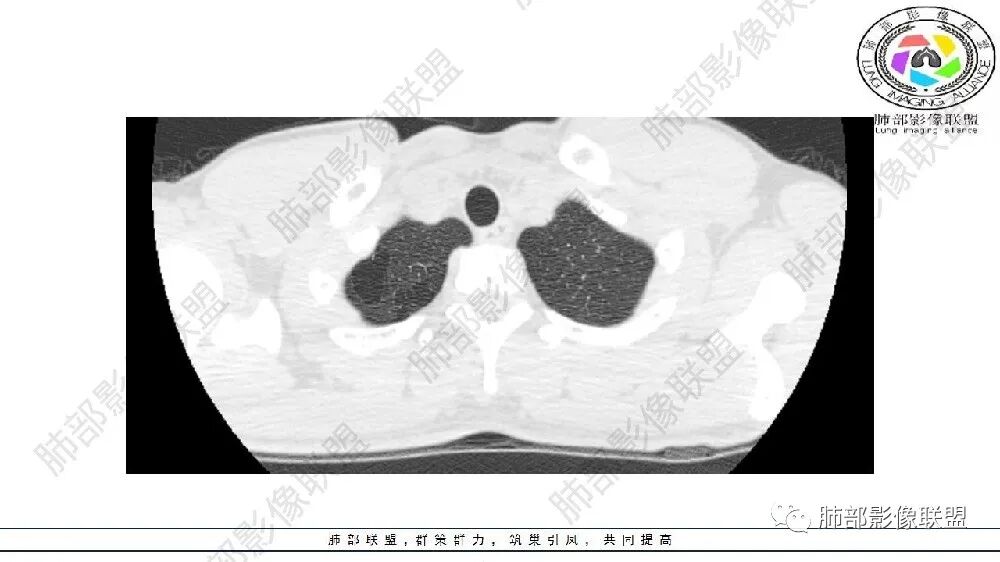

左肺下叶多发大小不等囊腔,部分有粘液栓,周围伴有磨玻璃影,左肺下叶基底干支气管未见,双肺尖可见多发局限性透亮区,青年男性,考虑先天性气道或肺部发育畸形,支气管闭锁?CPAM?鉴别肺隔离症。

左肺下叶多发薄壁囊性病灶,血管贴边,并多发增粗的血管,还有一些斑片影,磨玻璃影;两肺尖也有薄壁囊性病灶;病史咳嗽咳痰,痰中带血,跟老师们考虑肺隔离症伴感染,鉴别LIP

闭锁?附近没有大片肺气肿,不符合。为啥没有一元论?因为上肺病灶与左下叶病灶表现完全不同,一个是单纯低密度影,无壁;一个是管状+血管畸形

估计上肺病灶不会处理,所以忽视掉